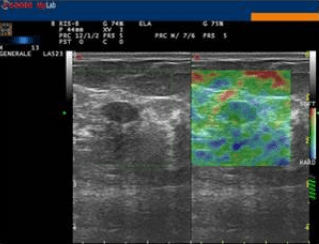

Presso lo studio di ecografia di Campobasso si esegue l'elastosonografia, o elastografia, l'ultima nata tra le applicazioni nel campo della diagnostica ad ultrasuoni. Essa si affianca alle applicazioni tradizionali dell'ecografia, come l'ecocolordoppler, aumentandone l'efficacia diagnostica, in quanto in grado di fornire informazioni sul grado di elasticità o di durezza di un tessuto o di un nodulo, rispetto ai tessuti sani circostanti.

Essa si basa sul principio secondo cui la compressione del tessuto in esame, esercitata dalla sonda ecografica, produce una distorsione, minore nei tessuti duri, quali quelli neoplastici o fibrotici, e maggiore in quelli soffici.